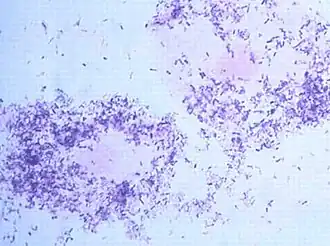

![]() Морфотипы Gardnerella vaginalis во влагалищном мазке, под микроскопом. | |

Баллы Nugent основаны на результатах микроскопии мазка, окрашенного по Граму, с оценкой соотношения различных морфотипов. В настоящее время этот метод считается «золотым стандартом» в диагностике бактериального вагиноза. Ответ выдается в виде баллов от 0 до 10. Нормальное состояние биоценоза влагалища констатируют при 0—3 баллах, при 4—6 баллах — промежуточное состояние, более 6 баллов — бактериальный вагиноз. При анализе не учитываются морфотипы, не связанные с бактериальным вагинозом; клиническая интерпретация промежуточных состояний затруднена.

- Уровень III (Бактериальный вагиноз) — доминирует морфотип Gardnerella vaginalis и/или Mobiluncus; малое количество или полное отсутствие лактобацилл;